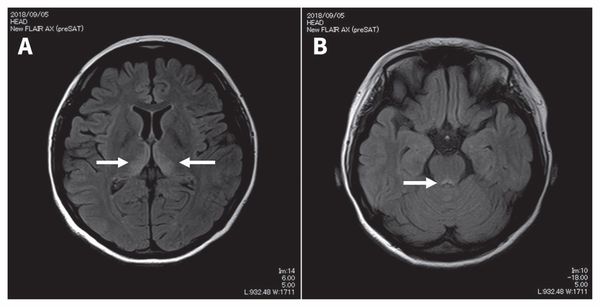

![Признаки энцефалопатии Вернике на снимке МРТ [22]](/pimg3/porazhenie-cherepnix-nervov-324574.jpeg)

Может применяться компьютерная томография (КТ) и магнитно-резонансная томография (МРТ). С помощью КТ определяют участки пониженной плотности в центральном сером веществе среднего мозга и в части таламуса, но в большинстве случаев этот метод не выявляет очаговой патологии при острой энцефалопатии.

Наиболее эффективный метод диагностики энцефалопатии Вернике — это МРТ. Интерпретировать результаты МРТ сможет только врач.

В половине случаев синдром Гайе-Вернике сопровождается генерализованным замедлением волн при ЭЭГ. РЭГ зачастую определяет диффузное снижение церебрального кровотока. КТ головного мозга, как правило, не регистрирует патологические изменения в церебральных тканях. МРТ головного мозга позволяет выявить гиперинтенсивные области в медиальных ядрах таламуса, мамиллярных тельцах, стенках III желудочка, ретикулярной формации, сером веществе, окружающем сильвиев водопровод, крыше среднего мозга. Зоны поражения склонны накапливать контраст, вводимый при проведении дополнительного контрастирования в ходе МРТ. В перечисленных областях могут определяться петехиальные кровоизлияния и признаки цитотоксического отека.